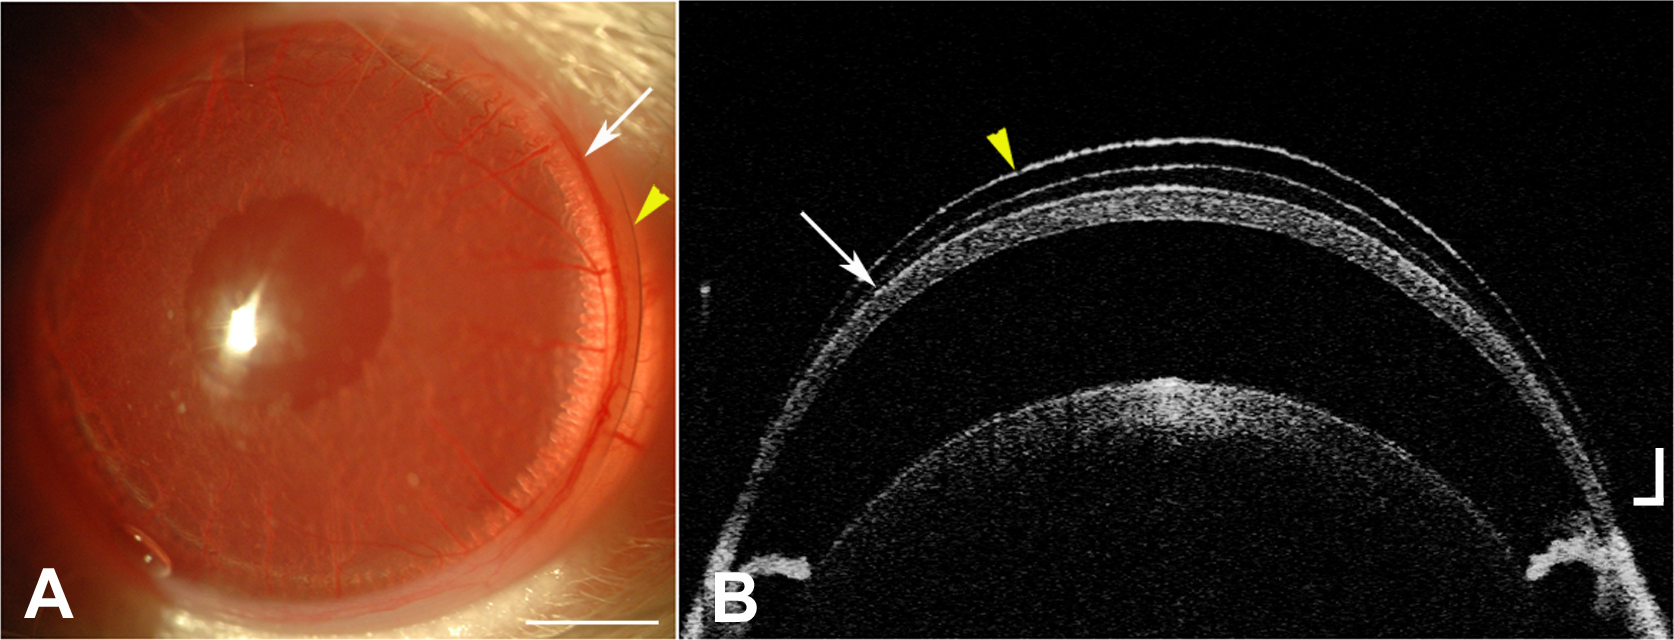

Figure 1. The custom made contact lenses fitted perfectly on the rat eye. A: A representative slit-lamp picture illustrates the rat eye with the contact lens in place. The yellow arrowhead points to

the margin of the contact lens and the white arrow to the limbus. B: The corresponding optical coherence tomography image shows the rat eye with the contact lens in place. The yellow arrowhead

points to the contact lens and the white arrow to the cornea. Scale bar=100 μm.